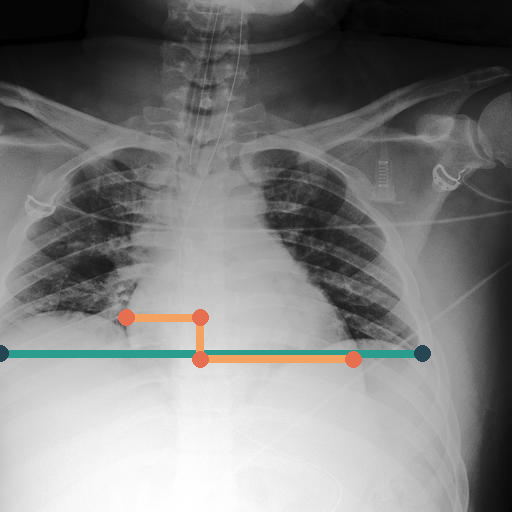

In Fig. 4, we show qualitative examples of the calculation of the cardio-thoracic-ratio for patients presenting cardiomegaly and not presenting cardiomegaly. For the case of the pathology, we see that the border of the heart is expanded, leading to a CTR above 0.7, whereas, for the absence case, the CTR is 0.4255.

When conducting a t-test, we get a value of 139.71 (p-value 0.0001) indicating a strong difference in CTR between positive and negative patients for cardiomegaly. We show this property in the violin plots on the left of Fig. 4, highlighting the CTR distributions for sex, age group, and pathology. Typically, the CTR for the presence and absence of cardiomegaly has noticeable shifts, with both respective means increasing with age. This average increase in CTR, however, becomes less in the age group of , with the disparity in mean CTR between cardiomegaly and no cardiomegaly reducing the older a patient gets. This result, in turn, lessens the insight of CTR with age. We observe this property for male and female patients. On the right of Fig. 4, we show the ROC-Curve for pathology classification based on the CTR score. We see a difference in the diagnostic performance of the CTR for female and male patients with an AuROC of 0.73 and 0.75.